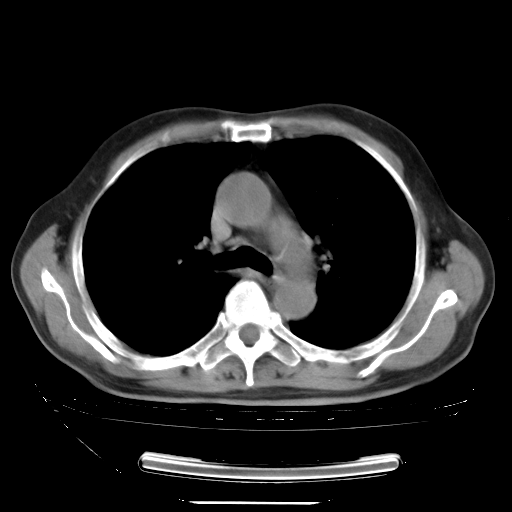

今天复查肺部CT,发现双肺广泛磨玻璃样改变。所以我把3月19日和5月9日相隔50天的肺部CT上传。请大家会诊。

5月9日肺部CT(在4月27日齐鲁医院肺部CT描述部分肺组织磨玻璃样改变,12天后肺组织广泛磨玻璃样改变)

大致读了系列胸部CT:纵隔窗无明显异常,肺窗:从4、27至今:主要是双肺中下野外带可见毛玻璃样改变,目前处于急性肺泡炎阶段,至于原因考虑1、结替组织或胶原血管性疾病所致?2、恶性疾病如恶组在肺部所致的表现或细支气管肺泡癌?3、药物或其它原因如肺蛋白沉着症所致肺泡炎目前不太可能?总之,明天就去请我院的呼吸科、感染科、血液科和临免专家会诊哈。